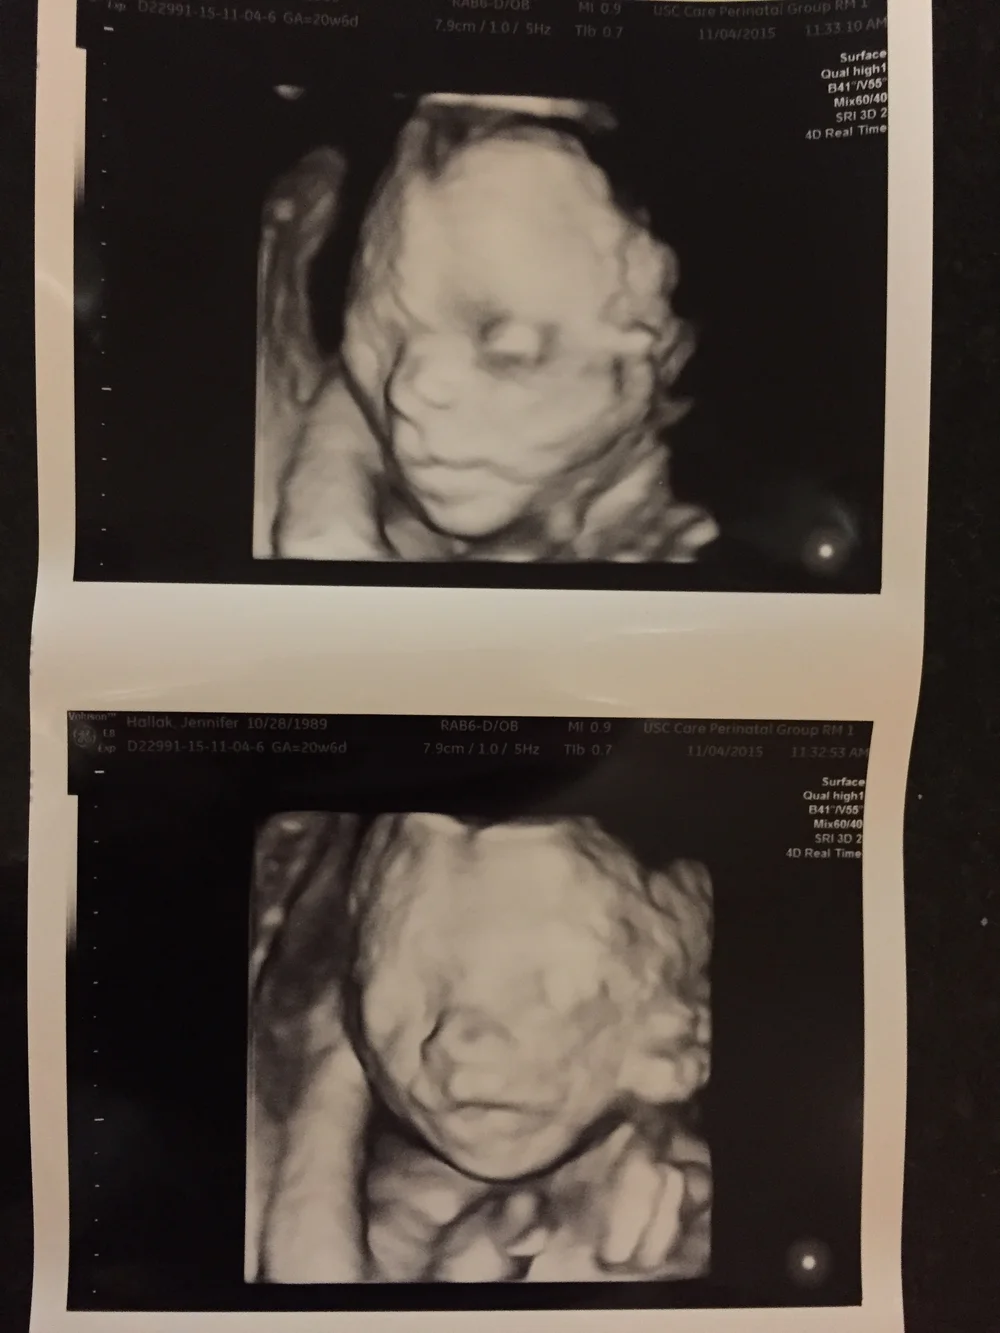

hair on ultrasound 20 weeks

On an ultrasound We went for the last growth scan last night. Hair is supposed to look whispy.

Hair on ultrasound 20 weeks Sunday July 17 2022 Edit. Why do you need a full bladder for 20 week ultrasound. The hair color of your baby cannot be determined or known on an ultrasound at this time.

Around 20 weeks fine downy hair starts to sprout from these follicles on the eyebrows upper lip and chin. Can you see hair on a 2D. I was so surprised that we could see it on a regular ultrasound.

The US tech is getting her head measurement and she said shes got a lot of hair already. I guess at the later ones there. All Curled Up At 18 Weeks Old Loveatfirstsight Baby Ultrasound Ultrasound 4d Ultrasound Pictures 4d Ultrasound.

Yes - I could see little spikes of hair on the babys head at a 32 week growth check. Do they check cervix at 20 week scan. Around 20 weeks fine downy hair starts to sprout from these follicles on the eyebrows upper.

Just had our 32 week growth scan and apparently baby girl has a tiny little tuft of hair at the back of her head. Apr 4 2020 at 125 AM.